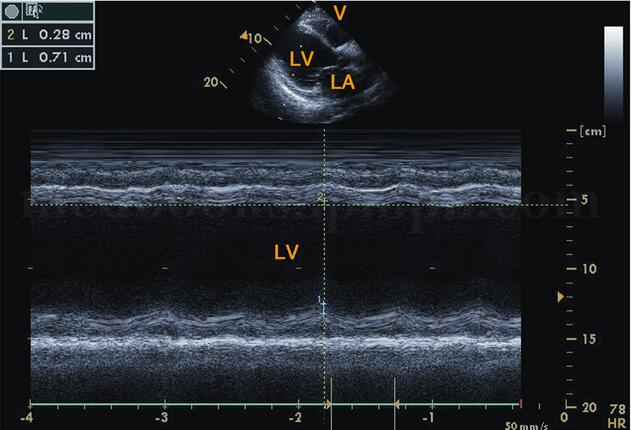

图2‐1‐183 二尖瓣口水平M型超声左室呈“大心腔,小瓣口”改变,E峰至室间隔距离明显增大

(1)二尖瓣波群见左室明显增大,右室扩大,二尖瓣前后叶开放幅度变小,呈“钻石样”改变,形成“大心腔,小开口”,但前后叶仍呈镜像运动。E峰至室间隔距离(EPSS)明显增大,一般>10mm。